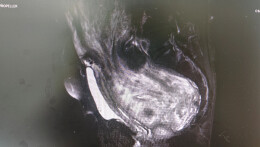

28岁突发心梗命悬一线!多学科协作+ECMO,让年轻患者重获“心”生